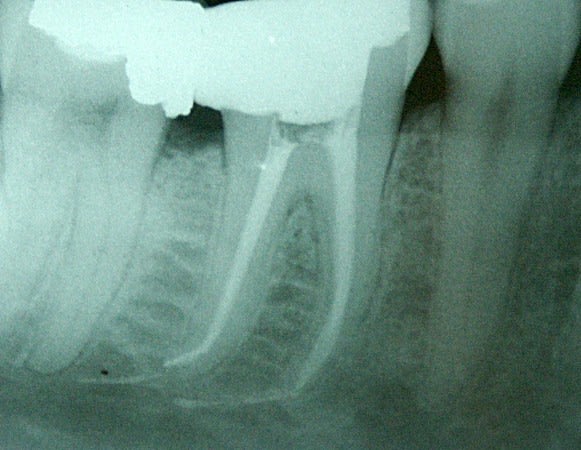

En parlant de F2, c'est le dernier instrument que j'ai cassé (en avril). Deux en toute cette année.

Endo sur un patient bruxomane avec une rétraction pulpaire bien marquée et des triangles dentinaires fortement prononcés.

Le F2 cassé est situé dans le canal DL de la 36 dans le crochet apical.

Si on en croit l'avis de stéphane, le pronostic d'une endo avec un instrument fracturé en fin de préparation + bonne désinfection préalable + champ op + pas de LPA préexistante + obturation étanche dans la foulée, n'est pas si mauvais, voire presque équivalent à un traitement sans instrument fracturé.

Dommage car il n'était pas moche ce traitement... (4 canaux).

P.S: aucune suite post op.